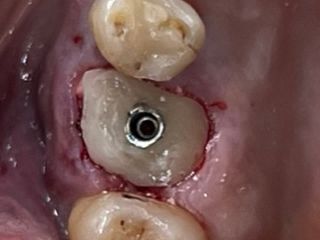

8. Occlusal view of the composite socket sealing with a 3mm provisional titanium retained SSA as fabricated by Gary Finelle.

8

9. Intra oral view with the SSA in place.

9